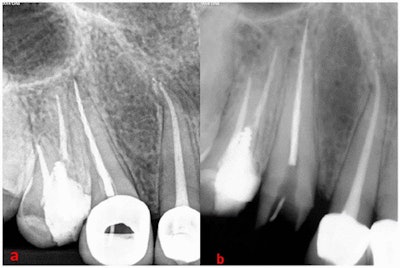

Etching needle with a K file as an extraction device (a) and etching needle engaged around the separated instrument and interlocked with the K file (b).Clinicians inserted the etching needle into the canal of the tooth and interlocked it with the large separated instrument. Then, a hand file was inserted into the needle lumen, which shackled the separated instrument. The fragment of the rotary file was removed from the patient's tooth after three tries using this method, according to the authors. An ultrasonic tip was used to remove the small instrument in the pulp chamber.

Separated instrument after it was removed from the canal. The removed separated instrument by hollow tube-based extractor (a) and (b) the length of the fragment was approximately 16 mm (b).To prevent separation of NiTi rotary instruments, the case report authors summarized the following preventive measures for clinicians: